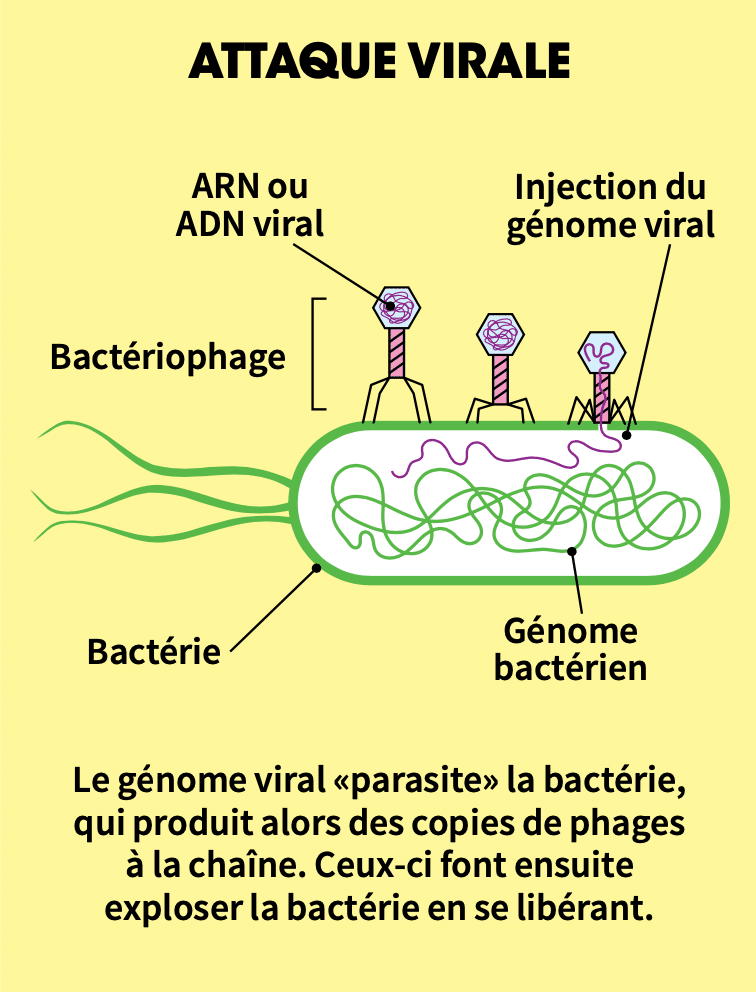

Les bactériophages attaquent leur cible selon différentes stratégies. Certains emploient une attaque directe : ils se fixent à la bactérie, y pénètrent, s’y multiplient, puis la font exploser en libérant de nouveaux bactériophages. C’est ce qu’on appelle le mode lytique.